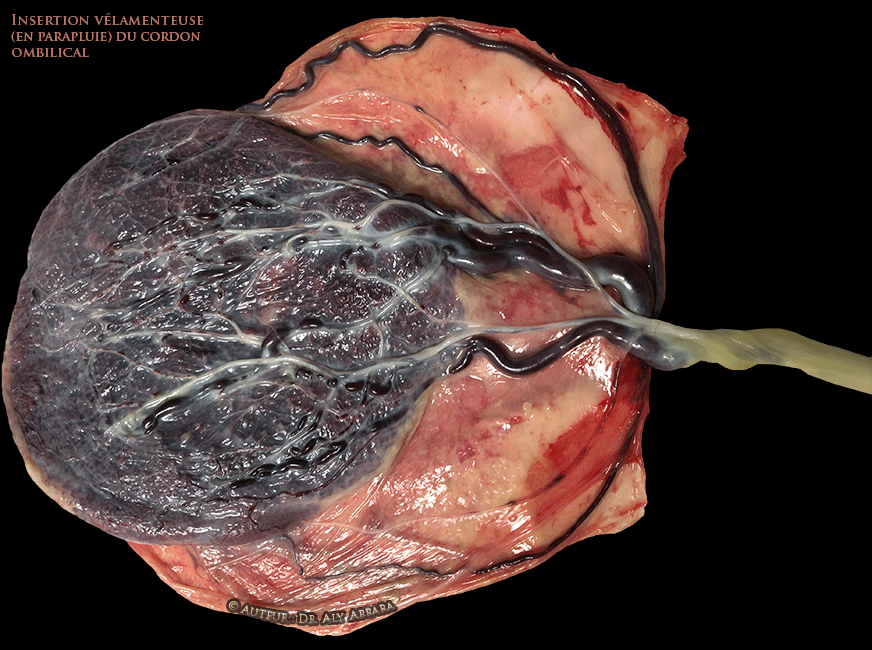

• L'insertion vélamenteuse (ou en parapluie) ("1", "2", vue globale, vue partielle ; Echographie : insertion vélamenteuse du cordon ombilical vue échographique) :

• Dans cette variété, l'insertion du cordon n'est pas sur le placenta, elle est sur les membranes libres , en dehors du placenta proprement dit et à plus de 2 cm du bord placentaire.

• Anatomiquement, en cas de l'insertion vélamenteuse du cordon, les vaisseaux sanguins du cordon :

• soit ils se ramifient sur les membranes, sous l'amnios ;

• soit les deux artères et la veine ombilicales parcourent les membranes, sous l'amnios puis elles se ramifient au contact du placenta.